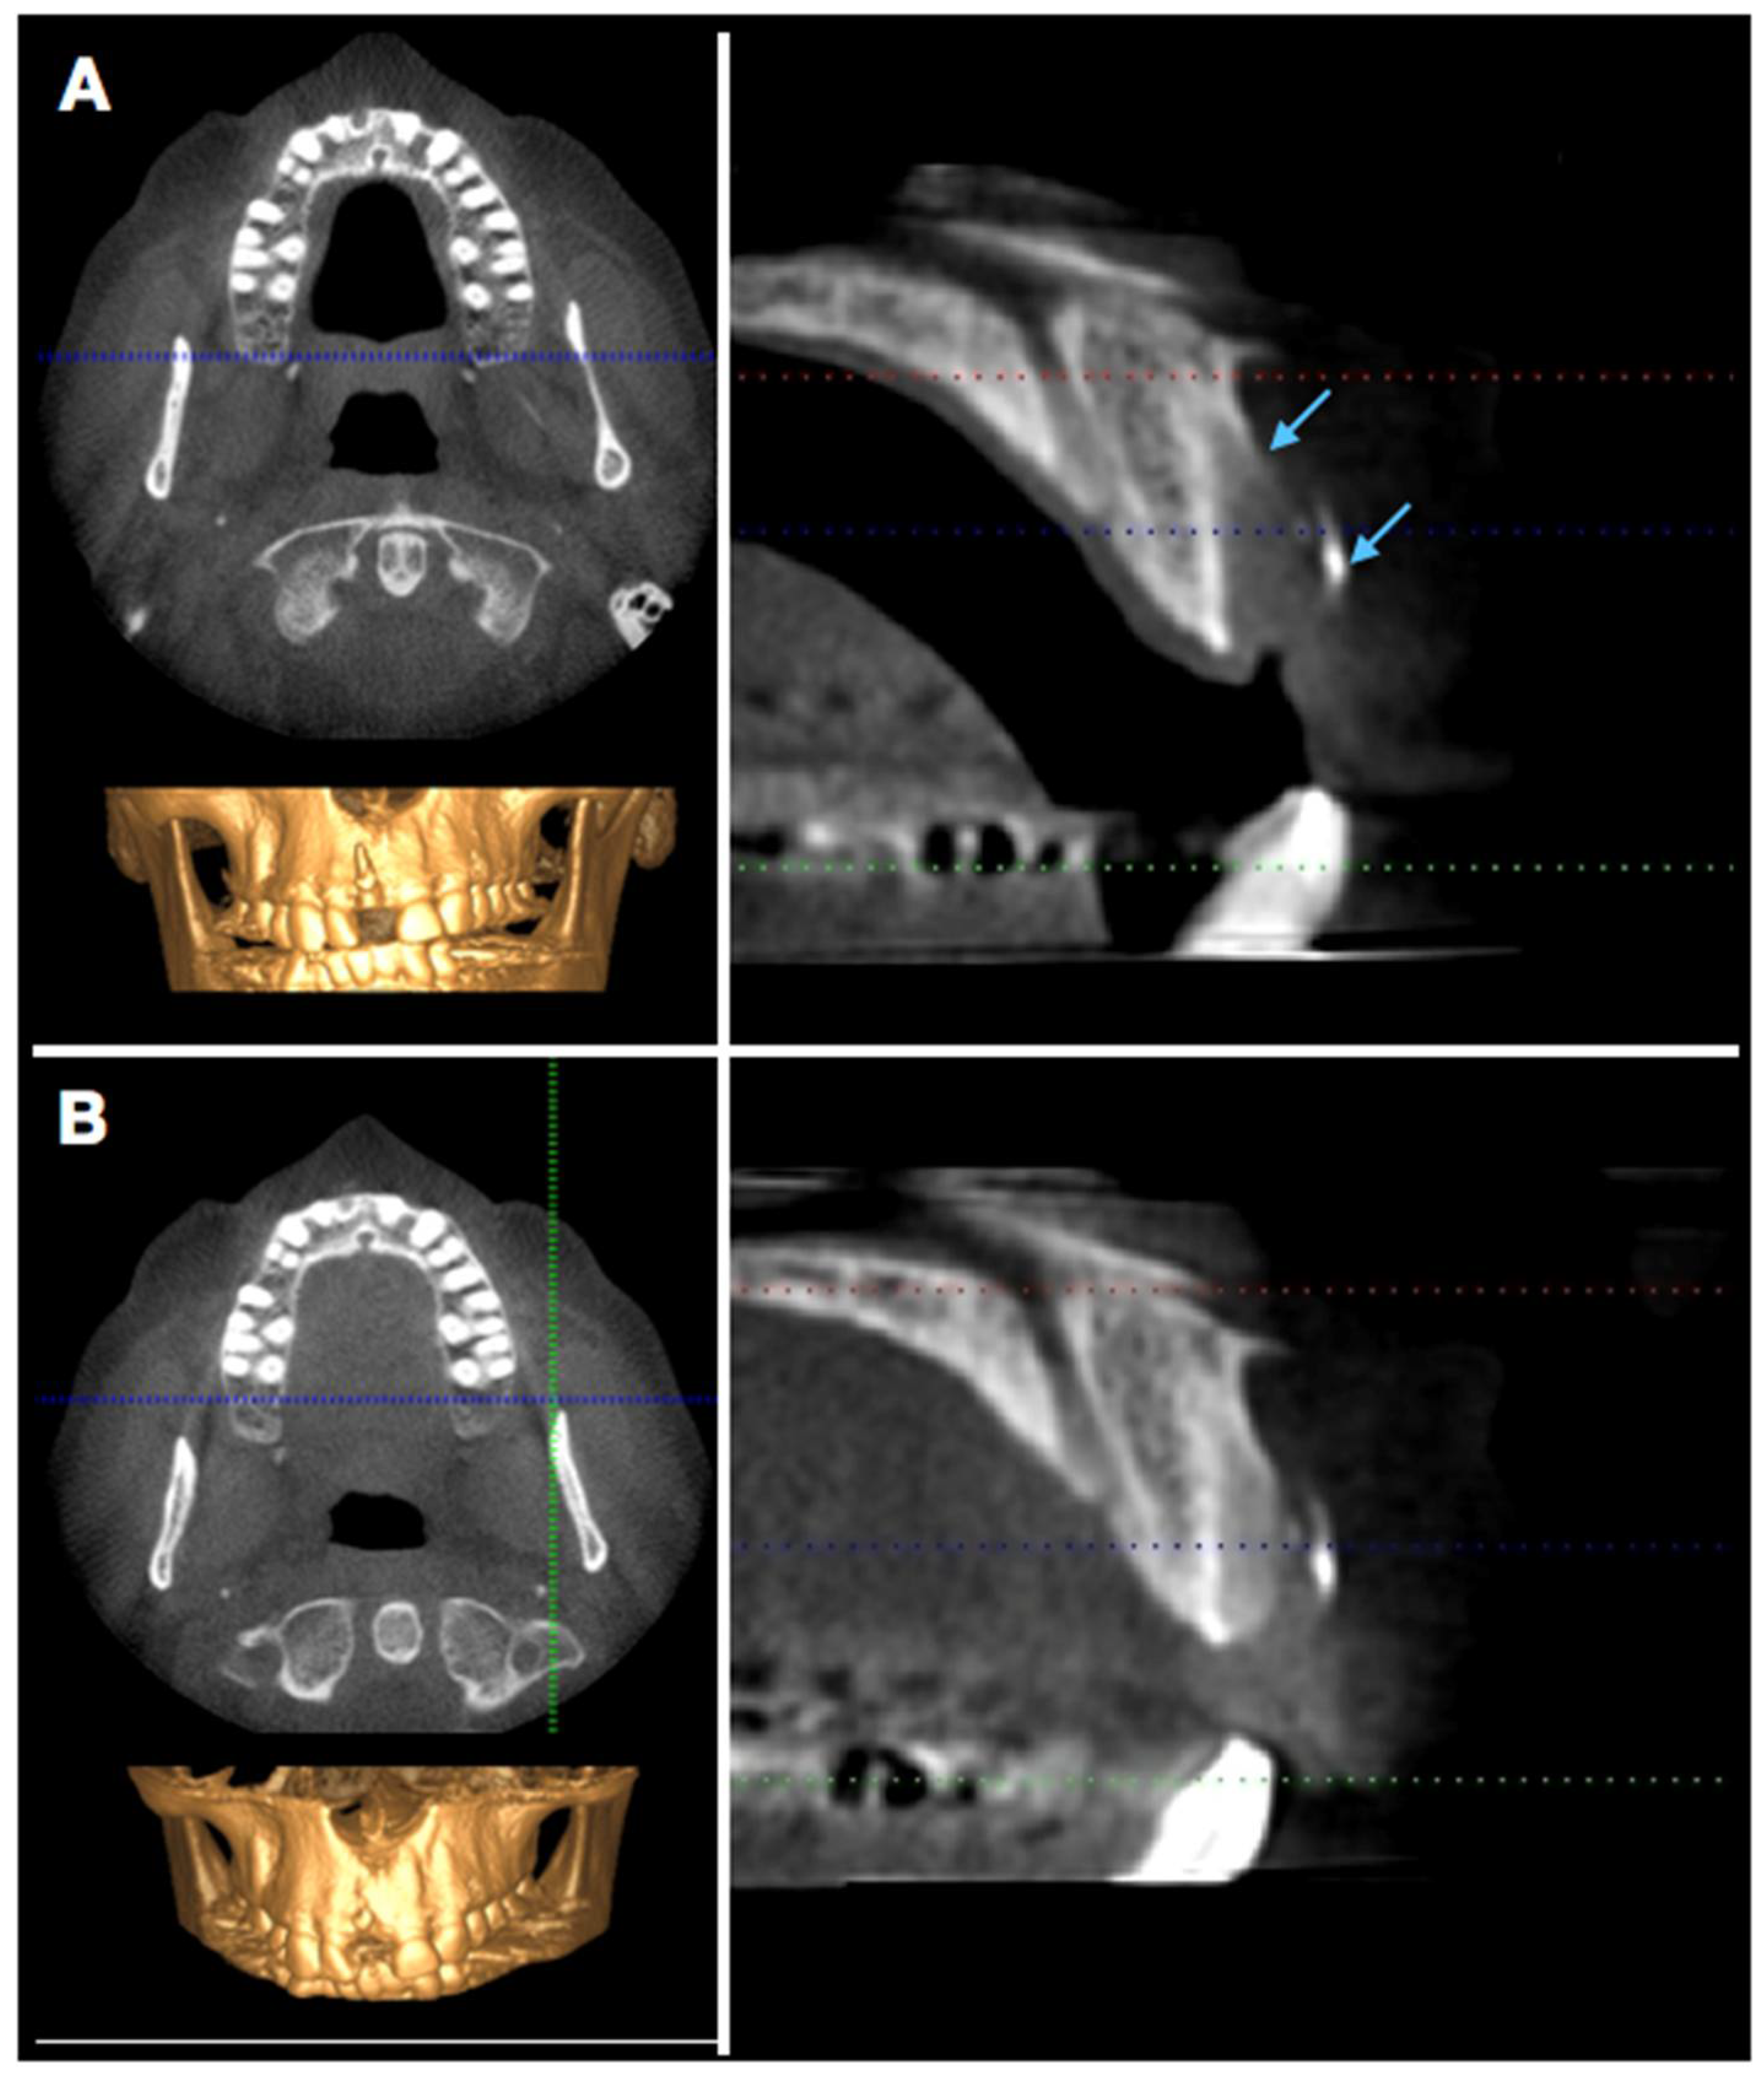

In order to visualize and assess the size of the defect and the extent of bony healing, a cone-beam computer tomography (CBCT) was performed 6 weeks and 16 weeks postoperatively (Figure 6). The extent of bone re-formation could be visualized non-invasively on the respective sections (Figure 6): In the first CBCT (6 w), bone fill was still incomplete, and the buccal bone lamella was not complete as well. The original fenestration was still identifiable with a vertical deficit of approximately 12 mm, which corresponded more or less to the clinical measurements and a mesio-distal bone defect, which accounted for 8 mm.

Figure 6.

Radiographic evaluation (CBCT) after 6 (A) and 16 (B) weeks. The arrows in panel (A) indicate the border of the buccal bone plate and the radiopaque membrane.

After another 10 weeks, remodeling was almost complete. However, the most coronal aspect still showed a small deficit. This was elucidated by the still existing radio-opaque remnants of the polylactic membrane (see lower arrow). The buccal wall below was following its contour, but some soft tissue space remains visible.